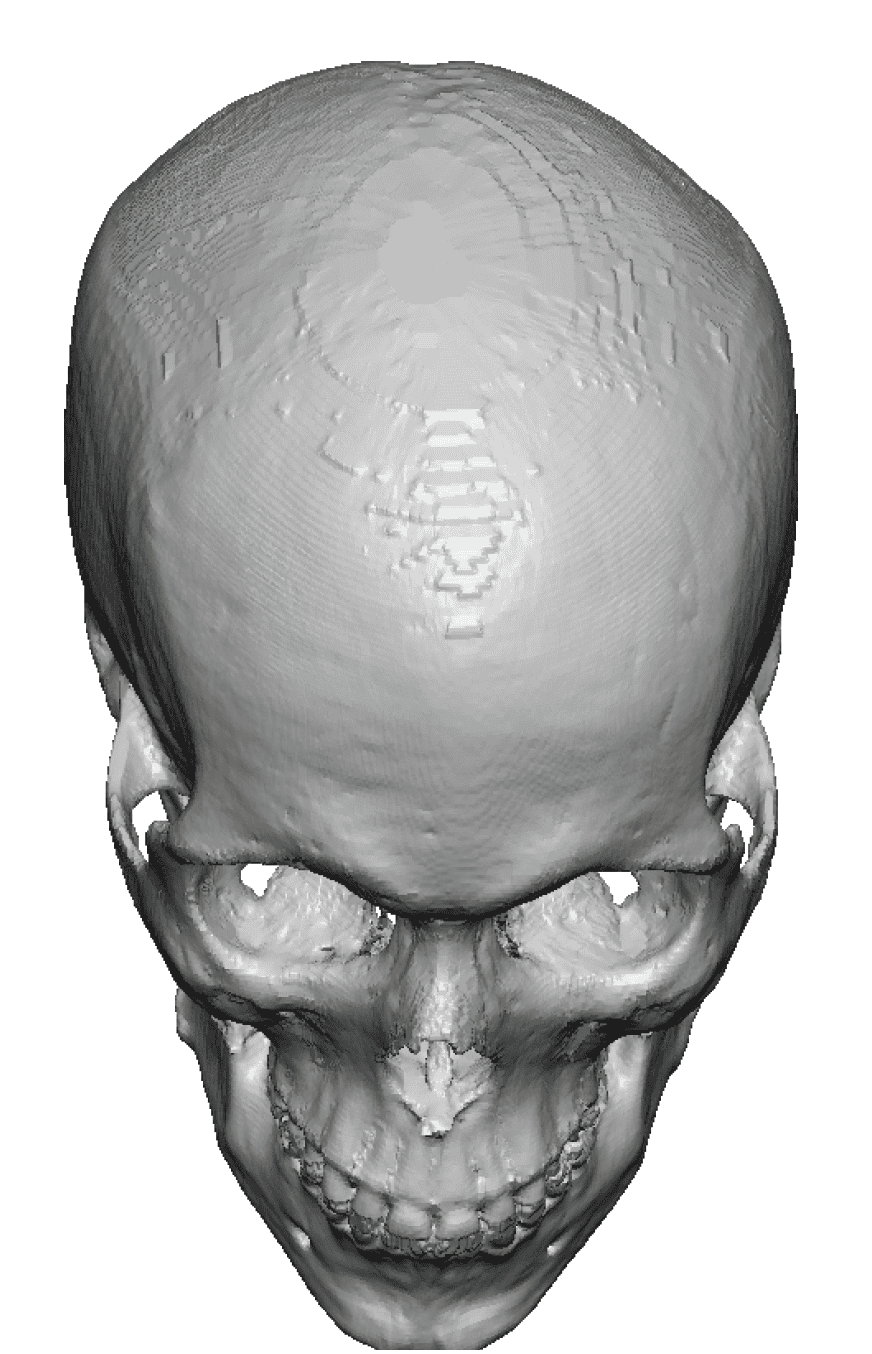

Patient 100

Desire for reshaping of an asymmetric flat back of the head in a shaved head male.

A combined back of the head reshaping procedure was done with a custom skull implant, sagittal ridge reduction and a right temporal muscle reduction.

Desire for reshaping of an asymmetric flat back of the head in a shaved head male.

A combined back of the head reshaping procedure was done with a custom skull implant, sagittal ridge reduction and a right temporal muscle reduction.